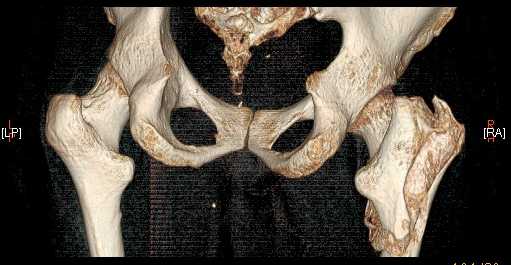

Доброго времени суток, уважаемые коллеги! Больному 45 лет. Лечили в сельской больнице на скелетном вытяжении 6 нед. по поводу межвертельного перелома бедренной кости с последующим наложением кокситной повязки еще на 2 мес.

С момента травмы прошло 5 месяцев, ходит с костылями без нагрузки, контрактуры в коленном и в тазобедренном суставах. Снимки во вложении. У нас мнения разделились. Показанием для открытого остеосинтеза мы считаем неустраненное ротационное смешение дистального фрагмента, которое может привести к нарушению биомеханики в тазобедренном суставе с последющими вытекающими последствиями. ЭОП на сегодняшний день недоступен нам, а остеосинтез угловыми пластинами, что можно попытаться, имеет определенный риск. Как быть? Начать разработку в суставах и активизировать больного, что не было сделано до этого, или всё-таки оперировать? Будем рады Вашим советам.

Никаких особенных проблем не видно, оперировать не видно, ради чего. Большого ротационного смещения нет, тазобедренный сустав - шаровидный, такие смещения прощает. Укорочение есть, но небольшое.

A что Вы думаете по поводу консолидации? Если имеется, почему до сих пор ходит с костылями? Если нет - о какой разработке суставов идет речь? Судя по рентгенограмме - не срослось. По КТ - ткань розового цвета между отломками такая же, как та, что покрывает головку. Тоже вроде не срослось. Мужику 45 лет. Конечно оперировать.